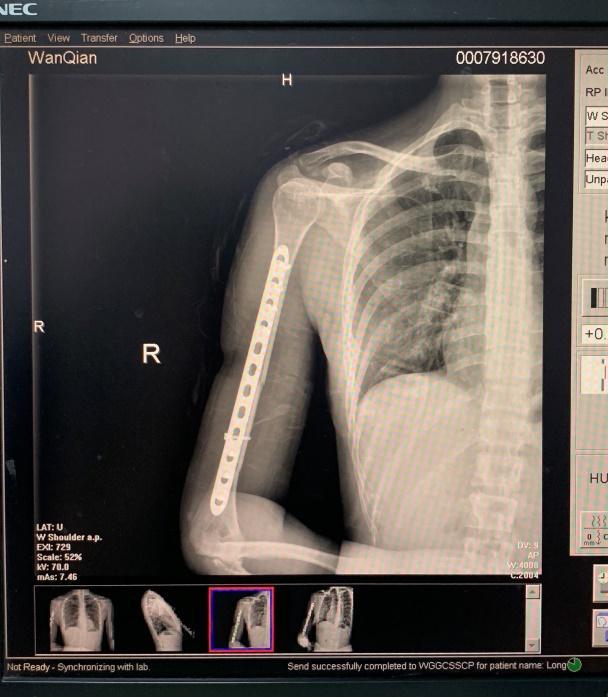

万茜车祸带伤上阵感动观众

而关注万茜的观众基本都知道 , 万茜在7月中旬因车祸受损了 , 导致右手粉碎性骨折进行手术 , 虽然医生宣布手术非常成功 , 但万茜由于神经受损 , 近期右手还是无法做过多的运动 , 并在努力康复中 。

之前有媒体预计可能万茜会因为车祸错过《乘风破浪的姐姐》最终成团 , 也会在近期内错过许多业务机会和表演 , 但现在看来 , 坚强的万茜什么也不会错过 , 凭借强大的意志力便能克服一切困难了 。

万茜|万茜罕见跨界做主持,与何炅同台飙戏,带伤上青春芒果夜感动观众。而这次2020年青春芒果夜 , 万茜带伤上阵的确让观众非常感动 。 当然 , 这次晚会的阵容可谓相当强大 , 参与的明星有蔡徐坤、蓝盈莹、黄晓明、朱一龙、欧阳娜娜等等 。

万茜|万茜罕见跨界做主持,与何炅同台飙戏,带伤上青春芒果夜感动观众。万茜带伤上场担任青春芒果夜主持人 , 一身水绿色闪钻纱裙 , 你觉得姐姐的主持功底如何?